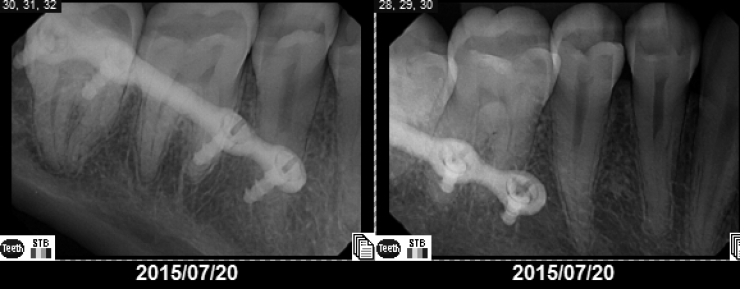

Because her jaw was misshapen, her teeth were not aligned well, and so she had to wear braces. She was insulted by regularly being called a 'monster'. She explains that some other students' parents even looked at her with disgust!

And indeed, with time after surgery, the transformation is impressive.